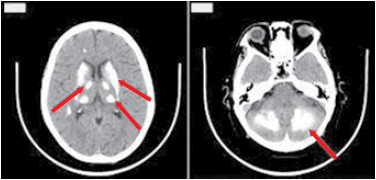

A tomografia de crânio a seguir mostra as lesões cerebrais características de um paciente portador de Doença de Fahr.

Assinale a alternativa correta que contempla outras doenças que podem cursar com o mesmo achado de imagem.